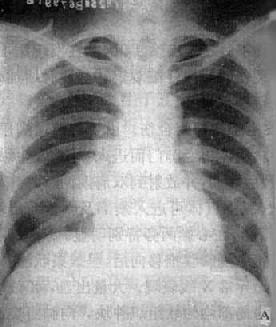

(2)亚急性或慢性血行播散型肺结核:系少量结核杆菌在较长时间内多次进入血流播散至肺部所致。患者抵抗力较强,症灶多以增殖为主,临床症状可不明显或有反复的发热、畏寒或轻度结核中毒症状如低热、盗汗、无力、消瘦等。

由于病灶系多次血行播散所形成,故X线表现为大小不一、密度不同、分布不均的多种性质的症灶(图3-1-23)。小者如粟粒,大者可为较大的结节状,主要分布于两肺上、中野,下野较少。早期播散的症灶可能已经钙化,而近期播散的病灶仍为增殖性或渗出性。本型结核发展较慢,经治疗新鲜病灶可以吸收,陈旧病灶多以纤维钙化而愈合。恶化时病灶可融合并形成空洞或逐渐转为慢性纤维空洞型肺结核。

图3-1-23 慢性血行播散型肺结核

两肺野布满大小不一、密度不同、分布不均的病灶,

下野较少,膈位置低而平